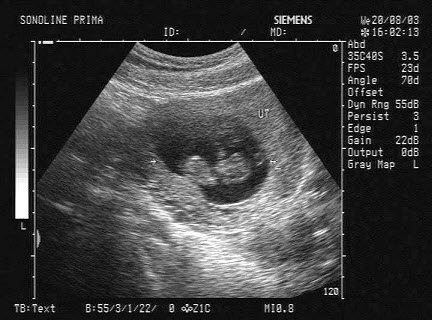

下图为宫内孕囊声像图,可见心管搏动,该胎儿至少大于多少周()